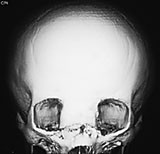

Cerebral CT med 3D-rekonstruksjon samt cerebral MR viste beindefekt mellom fremre skallegrop og mediale orbitavegg venstre side, samt en cystisk lesjon ca. 1,5 cm stor som dislokerte bulbus. Det var en stor og dyp utvidelse av fremre skallegrop. Normalt store ventrikler.

Pasienten ble vurdert av kraniofacialteamet og operert med kombinert ekstra- og intrakranial tilgang (fig 5).